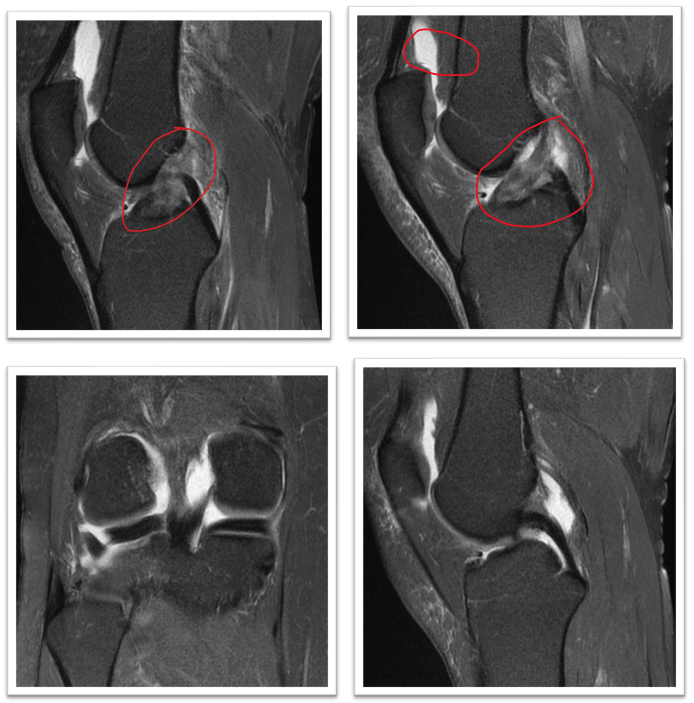

Example below:

Top right image 11 weeks after the injury clearly shows new ACL and the presence of synovial fluid promoting healing. Client: 48yrs old female after skiing accident